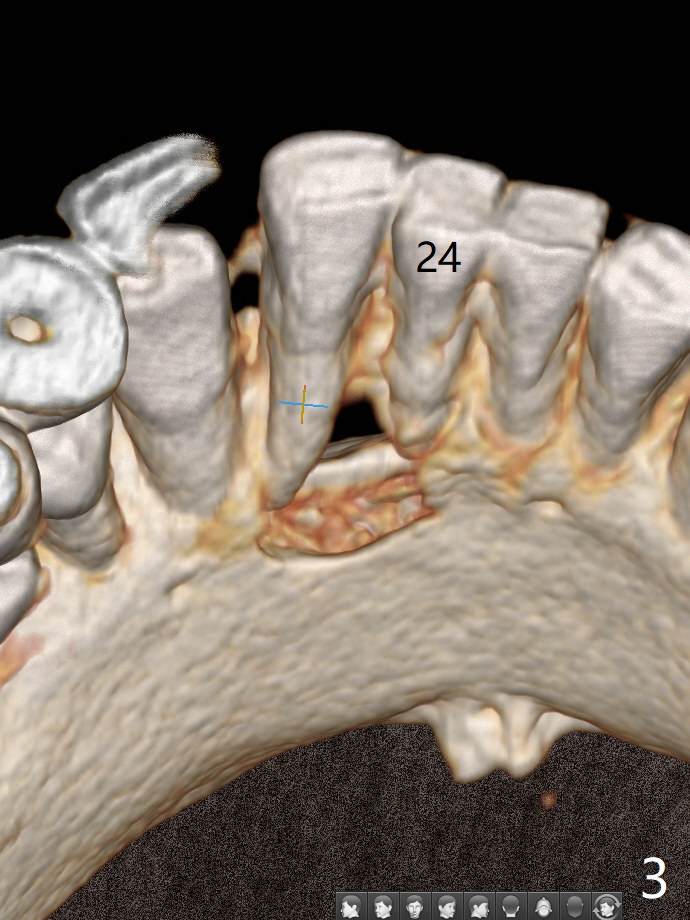

A 73-year-old woman has discomfort associated with #23 four months post Class V composite at #23-25 (Fig.1 C (*: Class V lesions)). Bone loss seems to be more severe lingually, especially at the crest (Fig.2 L). It appears that the apex of the tooth #24 is also in the large apical lesion (Fig.3). Class V composite is apparently continuous with the pulp at #25,24,23 (Fig.5-7). In contrast, Class V defect does not involve the pulp at #26 (Fig.4). If necrosis is confirmed clinically for #23 24 and 25, RCT will be conducted. Due to 7-day Amoxicillin taken for #3 implant, the patient feels that her tongue moves freely, as related to reduction in pain and swelling lingual to #23 (Fig.8 *). Endo ice test shows necrosis of #23 to 25. RCT is initiated at #23 (Fig.9) with buccal and lingual swelling. Endo may have to be at #24 with apicoectomy with PRF. The lingual swelling remains at #23, although there is no pain or purulent discharge 5 and 5.5 months post debridement (Fig.10,11). RCT is finished (Fig.12). Apicoectomy is pending with PRF. Less aggressive curettage will be done at #24 to maintain apical blood supply. Vitality tests have been done without conclusion.